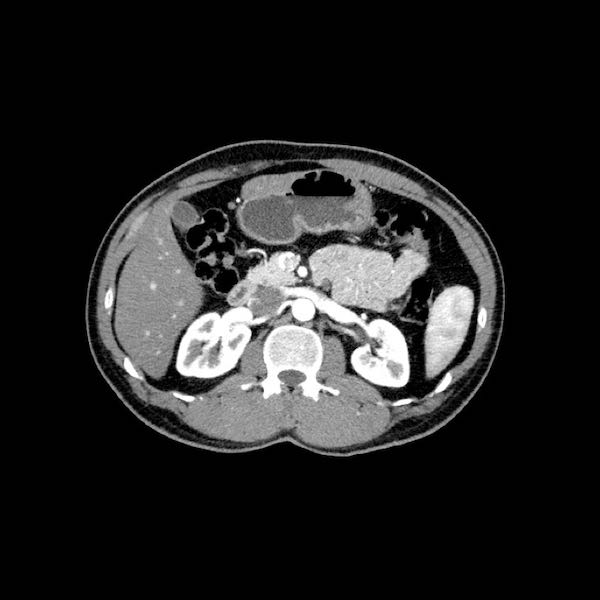

Dấu hiệu giọt nước mắt. Khối u lớn ở thân tụy, tiếp xúc 90 – 180 độ với SMV, đồng thời gây biến dạng SMV thành hình giọt nước mắt, rất nghi ngờ xâm lấn.

Các thay đổi hình thái gợi ý xâm lấn mạch máu

- Dấu hiệu giọt nước mắt (Teardrop sign)

Chỉ sự thay đổi hình dạng của tĩnh mạch cửa (PV) hoặc SMV từ hình bầu dục hoặc tròn sang hình giọt nước mắt. Điều này có thể do khối u bao quanh hoặc do xơ hóa lân cận kéo căng mạch máu. - Bất thường bờ viền mạch máu